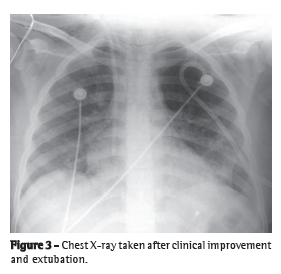

The use of venovenous ECMO was recommended, the right femoral and left jugular veins were cannulated with 20-F catheters, and ECMO was started. After having been stabilized, the patient (with the ECMO system still in operation) was transported by ambulance to the general ICU of the HC-FMUSP. Her Simplified Acute Physiology Score 3 before ICU admission was 79, and her Sequential Organ Failure Assessment score was 15, demonstrating the severity of her clinical status and the high risk of death. Figure 2 shows a chest X-ray taken immediately after ECMO initiation. A large quantity of blood in the tracheal aspirate, together with the decreased hemoglobin concentrations and bleeding disorder (Table 1), was suggestive of a diagnosis of alveolar hemorrhage. Support with ECMO was maintained for six days, during which the patient received polymyxin and intravenous immunoglobulin for the treatment of pneumonia and the underlying disease, respectively. During that period, the patient required dialysis with continuous hemofiltration, and she was weaned from the noradrenaline. Because of her bleeding disorder, we chose to maintain the patient on ECMO without anticoagulation. No ECMO-related complications occurred. The patient presented with hypertensive pneumothorax in the left lung and therefore underwent pigtail catheter drainage (Figure 3).

During ECMO use, we performed daily autonomy tests, which consisted of attempts at maintaining gas exchange without ECMO for 1 h at the same pressures and frequencies, with an FiO2 of 60%. For the first five days, the patient developed severe hypoxemia whenever the extracorporeal support was reduced. On the sixth day, after a satisfactory autonomy test result, ECMO was discontinued, and the ventilatory support was progressively reduced. On the eighth day, the patient was extubated. Figure 3 shows a chest X-ray taken after extubation. On postadmission day 14, the patient was discharged to the infirmary. She was using an oxygen catheter at 2 L/min, and her SpO2 was 98%.